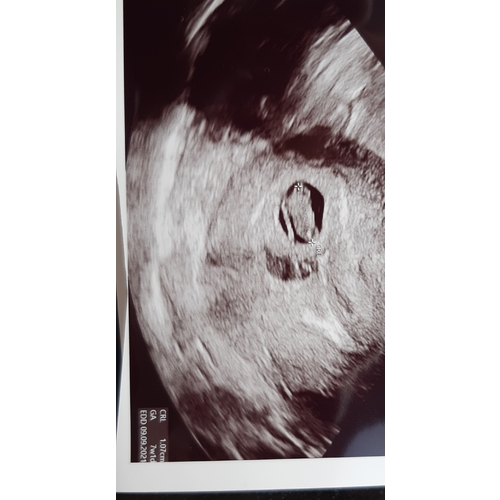

Dit was mijn echo met 6+5